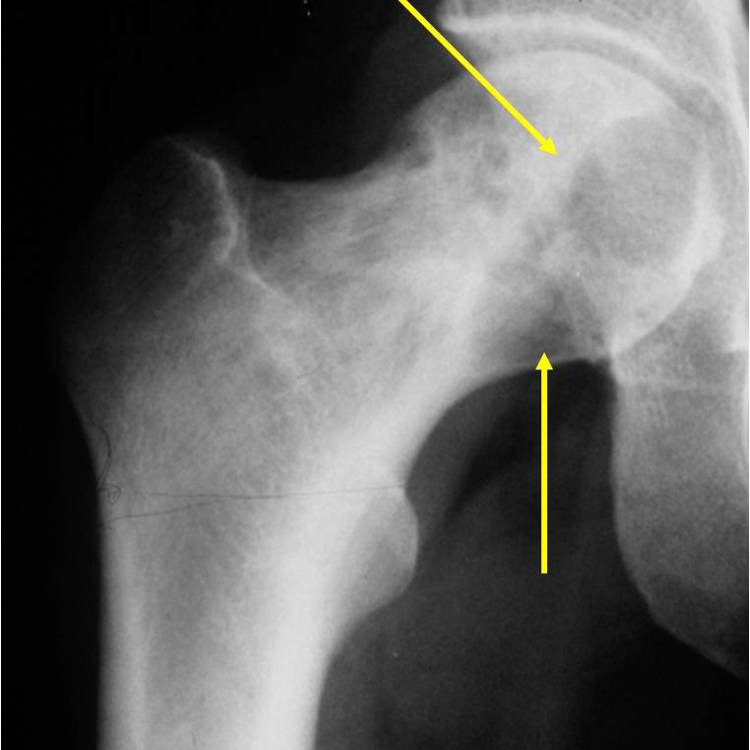

X-Ray of Clear Cell Chondrosarcoma

On an X-Ray, also called a radiograph, a clear cell chondrosarcoma can be diagnosed by looking at certain features. Most commonly seen in a clear cell chondrosarcoma is usually osteolytic, expansile lesion, that may be focally calcified, often a sharp interface between tumor and surrounding bone and the overlying cortex is usually thin, but intact.